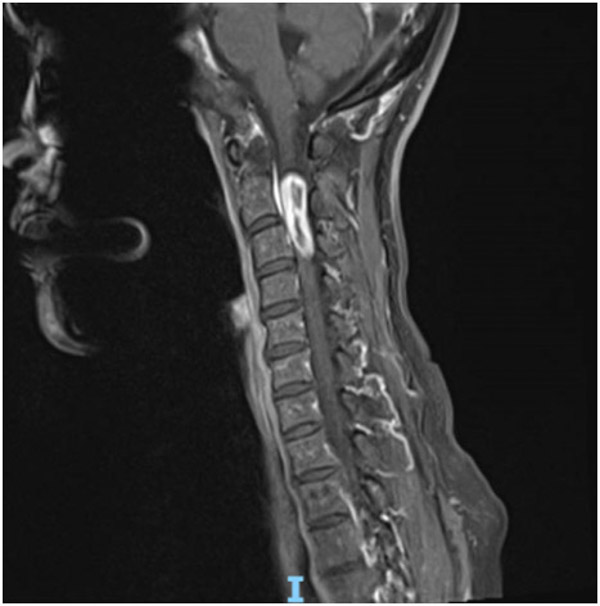

58歲的蘭女士因胸部束縛感2年,左上肢麻痛1年在當(dāng)?shù)蒯t(yī)院就診,經(jīng)檢查發(fā)現(xiàn)患者高位頸髓區(qū)域有一顆巨大腫瘤,手術(shù)風(fēng)險(xiǎn)大,術(shù)后出現(xiàn)高位截癱的可能性非常高。為求更好的治療方案,蘭女士輾轉(zhuǎn)了多家醫(yī)院,最終來(lái)到了柳州市人民醫(yī)院神經(jīng)外科。

了解到患者的病情后,神經(jīng)外科治療團(tuán)隊(duì)迅速作出了判斷:此類腫瘤常規(guī)手術(shù)要采用至少15cm以上長(zhǎng)切口切除,切除多節(jié)段椎板影響脊柱的穩(wěn)定性,需要行內(nèi)固定手術(shù),頸1、2內(nèi)固定將嚴(yán)重影響患者的頸部活動(dòng),為日后生活帶來(lái)諸多不便。

于是神經(jīng)外科治療團(tuán)隊(duì)便針對(duì)患者的特點(diǎn)制定了手術(shù)方案,采用改良側(cè)方肌間隙半椎板入路,僅需6cm手術(shù)切口,術(shù)中電生理監(jiān)測(cè)在顯微鏡+神經(jīng)內(nèi)鏡下全切腫瘤,這種方法可精準(zhǔn)的暴露頸髓側(cè)方及腹側(cè)的腫瘤,避免頸髓的牽拉,減少了手術(shù)創(chuàng)傷,縮短手術(shù)時(shí)間,后路絕大部分椎板、肌肉及韌帶保留,降低了患者術(shù)后椎柱失穩(wěn)的風(fēng)險(xiǎn),無(wú)需內(nèi)固定。

聽(tīng)了醫(yī)生的解釋后,蘭女士欣然決定進(jìn)行手術(shù)治療,困擾自己的2年多的病痛終于有了妥善的解決辦法。手術(shù)非常成功,術(shù)后癥狀便得到了緩解,2周后患者痊愈出院,目前頸部活動(dòng)自如,無(wú)任何后遺癥。